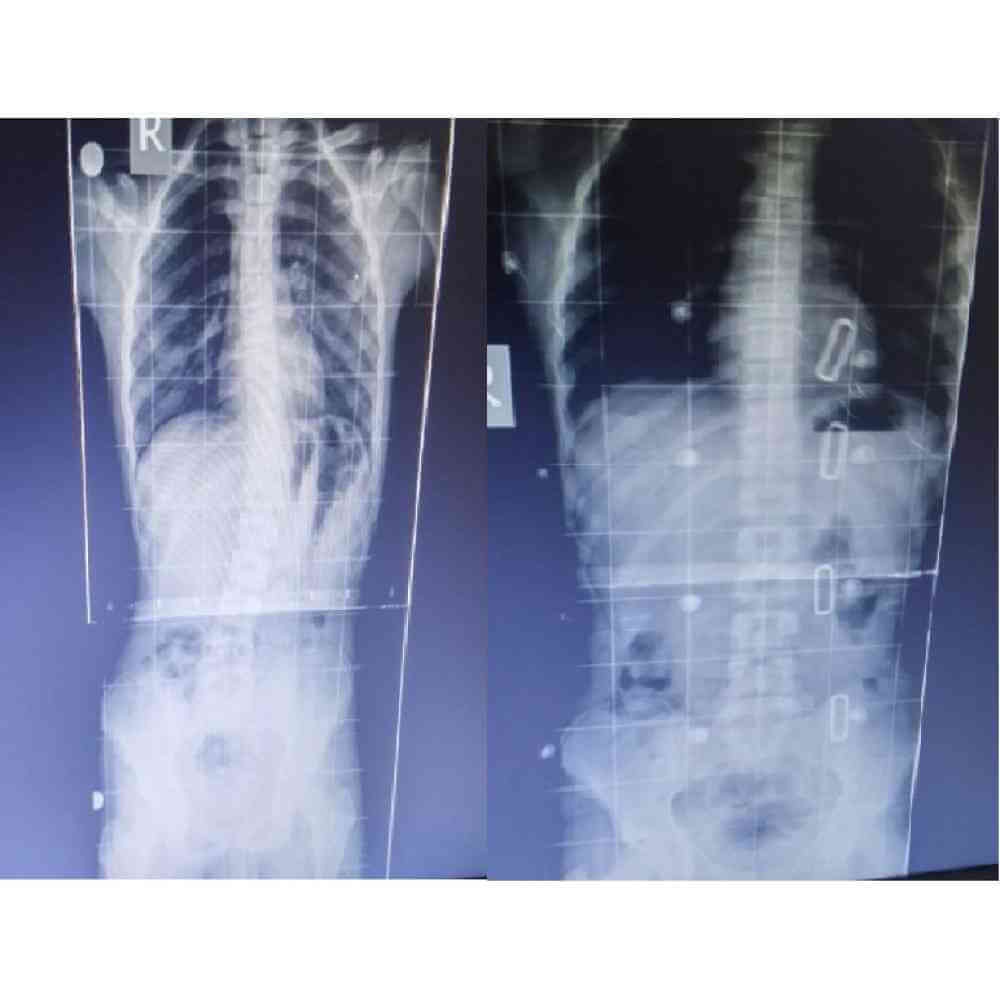

Nesa Ortopedi firmamızın bünyesinde skolyoz hastalarımızın ölçüleri son teknoloji scanner (tarayıcılar) ile alınmaktadır. Kişilerin skolyoz korseleri , alınan bu ölçüler ile röntgen ve fotoğraları da dikkate alınarak 3 boyutlu olarak tasarım programında tasarlanmaktadır. Tasarım sonucunda ise korseler hatayı minimize eden Cnclerde işlenmektedir. Sonuç teknolojinin yardımı ile daha iyi sonuç verecek korse hastamıza üretilmektedir.